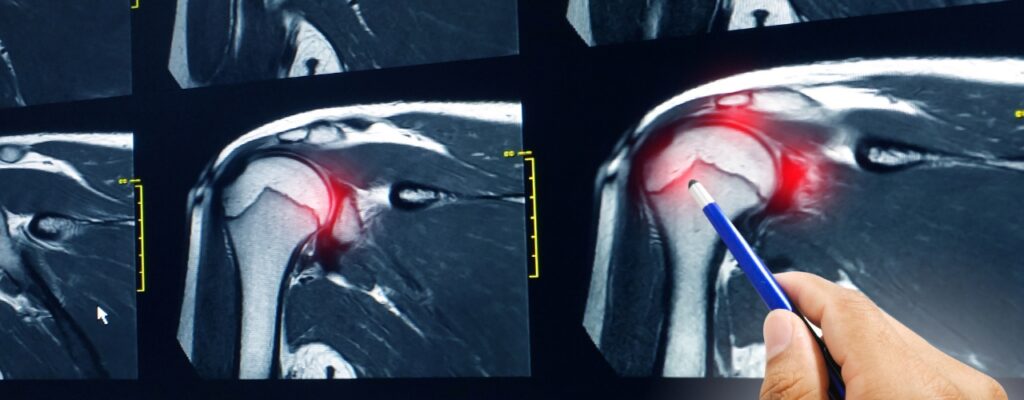

Rotators Cuff Injury